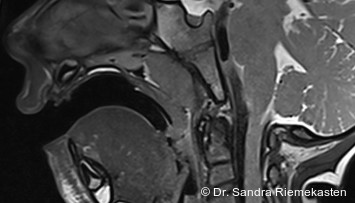

Anhand eines adulten Patientenfalls wird aufgezeigt, wie eine scheinbar neutrale Okklusion eine erhebliche skelettale Fehlrelation maskieren kann und welche weitreichenden Konsequenzen sich daraus für Diagnostik, Therapieentscheidung und Langzeitprognose ergeben. Fotos: © Prof. Dr. G. Polzar